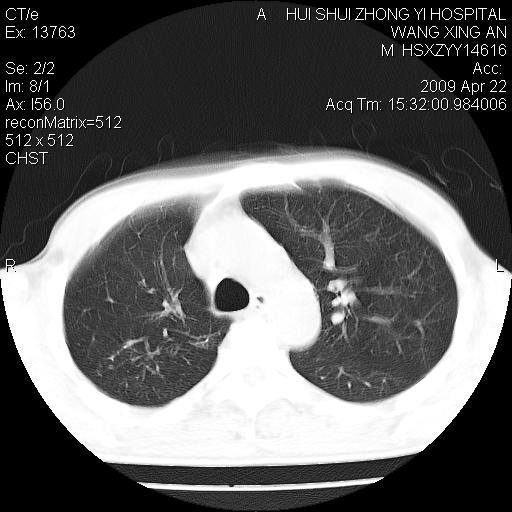

标题: CT19534:患者男、46岁咳嗽、胸痛半月。 [打印本页]

标题: CT19534:患者男、46岁咳嗽、胸痛半月。

考虑---右肺中心型肺癌继发下叶不张,少量胸水。

支持右侧中央型肺ca并右下肺不张、右侧胸腔少量积液。

1、右下肺中央型肺癌并右肺转移,右肺下叶不张。(肿块围绕右肺下叶支气管生长,致管腔闭塞右肺下叶不张;右肺有结节影)。

2、右侧胸腔积液。

3、右中上肺陈旧性肺结核(右肺见纤维化病灶及点状钙化)。

1)右肺中间段支气管癌并右肺下叶肺不张。2)右肺上叶、两肺下叶背段感染性病变。3)右侧少量胸腔积液。